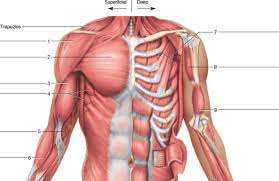

قیمت: 96٬000 تومان - دسته بندی فایل: پاورپوینتپاورپوینت آناتومی انسان

فروش ویژه پاورپوینت حرفه ای آناتومی انسان / تعداد اسلاید: 403 اسلاید

قیمت: 96٬000 تومان - دسته بندی فایل: پاورپوینتدانلود پاورپوینت آناتومی و فیزیولوژی

فروش ویژه پاورپوینت حرفه ای آناتومی و فیزیولوژی / تعداد اسلاید: 210 اسلاید